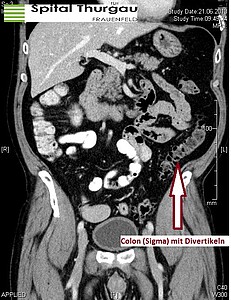

Ein Divertikel bildet sich aus Darmschleimhaut, welche sich durch kleine Lücken der muskulären Darmwand hindurchdrückt. Als Ursache geht man von einer Drucksteigerung im Übergang zwischen Sigma und Rektum (Hochdruckzone des Dickdarms) aus. Diese Divertikel nehmen im Alter zu, bei etwa 60-70% der 70-jährigen Patientinnen und Patienten ist eine sogenannte Divertikulose in der Darmspiegelung zu erkennen. Entzündet sich eines dieser Divertikel, spricht man von einer Divertikulitis. Meist kommt es zu Schmerzen im linken Unterbauch, teilweise begleitet mit Obstipation und Fieber.

Die Diagnostik beginnt auch hier mit der Anamnese und der klinischen Untersuchung. Der Bauchraum wird abgetastet, oft findet sich zum Druckschmerz eine tastbare Walze im linken Unterbauch. Die weitere Diagnostik der Wahl ist anschliessend eine Computertomographie. Hier können nicht nur Entzündungen, sondern auch kleinere Abszesse erkannt werden. Nachdem alle Befunde und die Blutwerte vorliegen, kann entschieden werden, welche Therapie möglich ist.